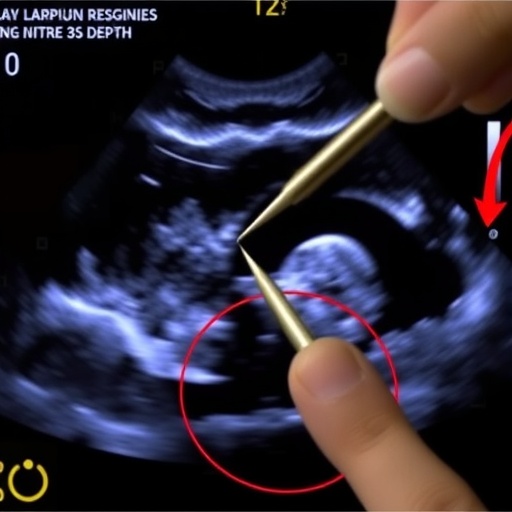

The study conducted by Choi and colleagues focuses on determining the optimal needling depth using state-of-the-art ultrasound imaging technology. This approach not only expands our understanding of acupuncture but also enhances the ability to provide evidence-based treatments. Traditionally, assessments of acupuncture techniques have been largely anecdotal. However, with advancements in imaging techniques, researchers can now visualize needle placement accurately and measure the specific physiological responses elicited by varying depths.

One of the crucial findings of the study is that the depth of needle insertion can significantly alter the psychophysical responses experienced by patients. Through the use of ultrasound imaging, the researchers were able to assess the effects of deeper needling on the surrounding tissues, including muscle and fascia. Understanding how these tissues respond to different depths opens the door to better therapeutic strategies and improved patient experiences.

The research highlights not only the physiological aspects of needling but also the psychological responses involved. Patients’ perceptions of pain and discomfort during acupuncture sessions can heavily dictate their overall experience and willingness to continue treatment. By visualizing needle placement and movement in real-time, clinicians can adjust techniques to minimize discomfort, potentially leading to enhanced patient satisfaction and adherence to treatment protocols.